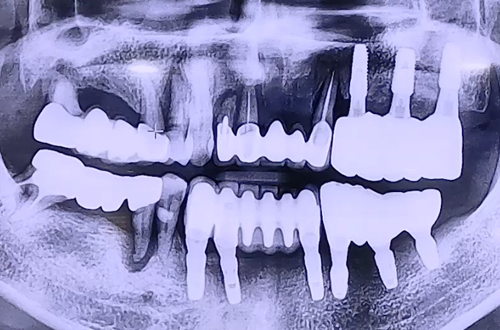

AFTER

불편한 치아들을 발치하고 임플란트를 단단히 심어드렸고,

임플란트는 굉장히 단단하게 잇몸뼈와 잘 결합되고 주변 뼈이식까지 잘 진행되었어요.

만약 심으려는 임플란트가 단단할 경우 당일에 바로 임시치아를 체결해 드리는데

환자분게서는 위 앞니 주변 잇몸뼈들이 약해서 즉시 임시치아 체결은 불가능했습니다.

따라서 위 앞니 임플란트를 잇몸 속으로 완전히 묻어두고 시간이 지나 스스로 굳게 하기로 하고

임시치아는 끼우고 빼는 타입으로 제작하여 드렸던 케이스입니다.